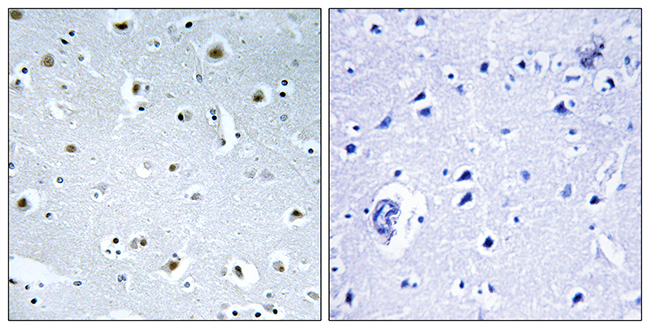

ApplicationsWestern Blot, ImmunoHistoChemistry

ReactivityHuman

- SizePrice